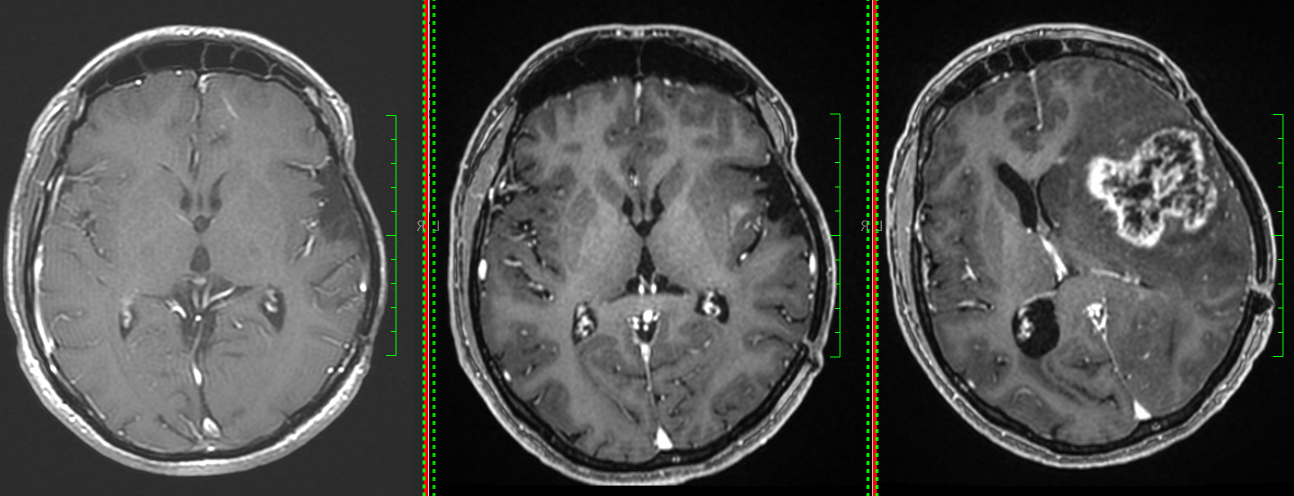

Astrocitom anaplazic grad III temporo-occipital drept

• RMN cerebral este metoda de elecție. Tumora apare ca o leziune hipointensă în T1 și hiperintensă în T2/FLAIR, cu captare neregulată de contrast.

• Constant se observă edem peritumoral și efect de masă.

Astrocitom anaplazic (grad III) temporal drept – RMN preoperator

Astrocitom anaplazic (grad III) temporal drept – RMN postoperator